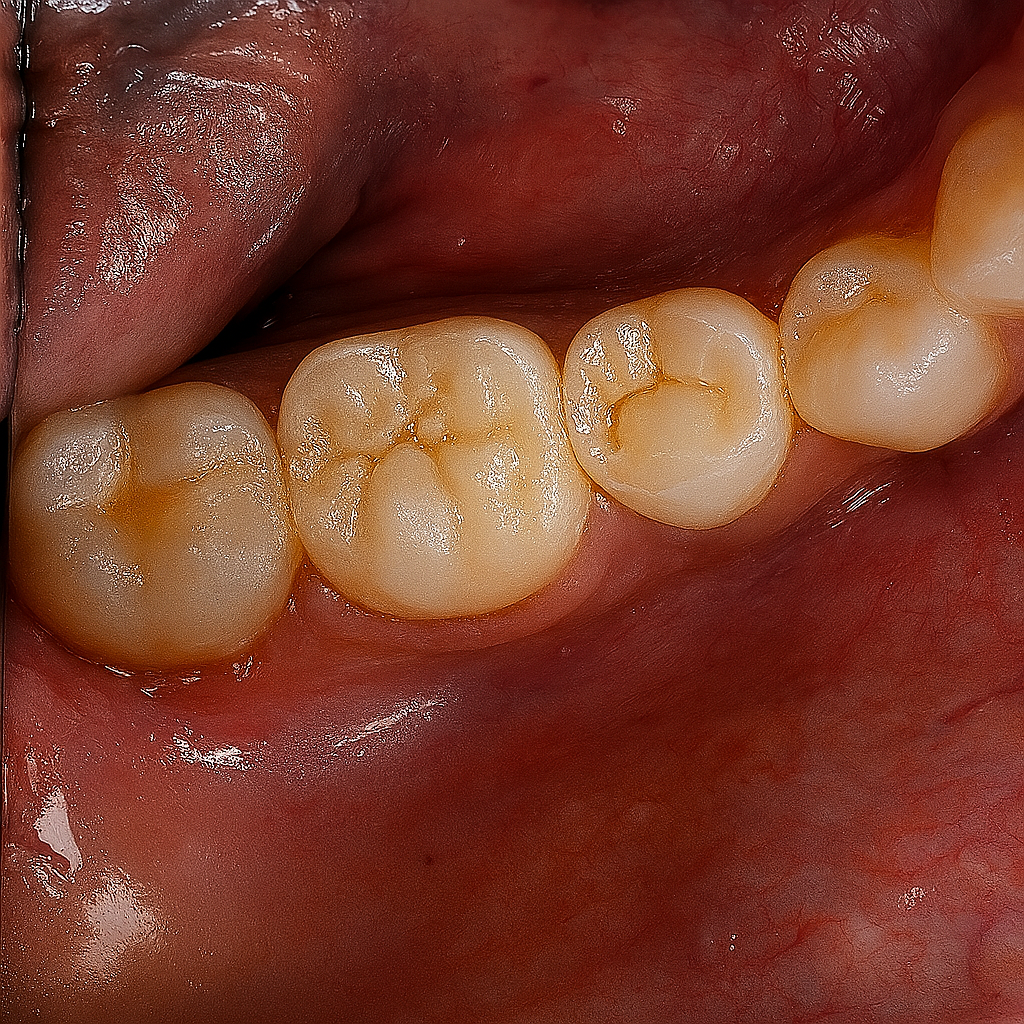

A full-coverage zirconia crown was fabricated to mimic occlusal morphology (Fig 4). Try-in confirmed marginal adaptation and occlusal contacts. Final bonding performed with Panavia V5 resin cement under isolation.

Radiograph confirmed ideal obturation, core adaptation, and marginal integrity (Fig 3). The final restoration blended esthetically and functionally with the dentition (Fig 5).

- Fig 4: Monolithic zirconia crowns ready for cementation.

- Fig 5: Final clinical result demonstrating functional and esthetic integration.